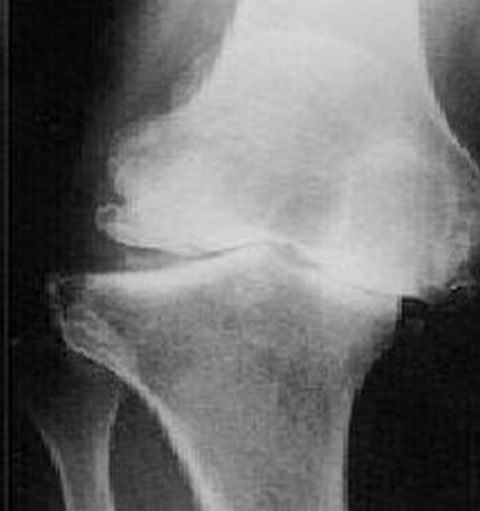

術前の膝。

って、レントゲンですが、。。。

ココまで曲がっていたので。。。

仕方ないやっぱ手術か。。。